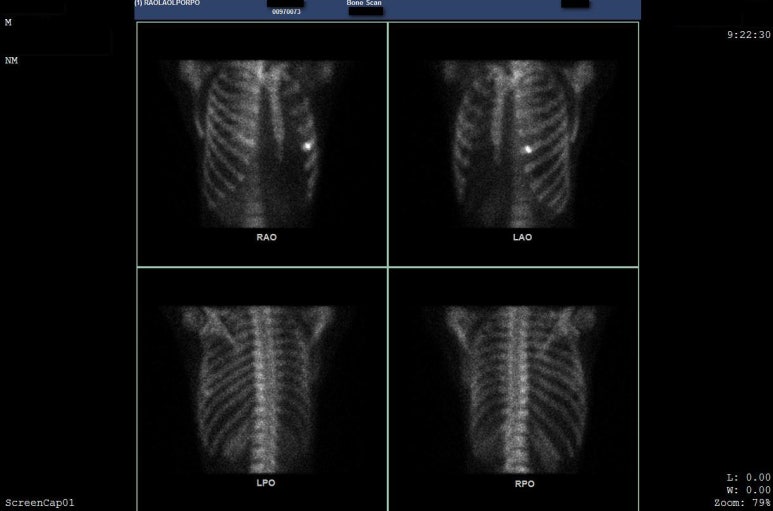

Bone Scan 검사를 진행했습니다.

해당 환자분의 Bone scan 검사

본 스캔 검사로

골절 확진을 받았습니다.